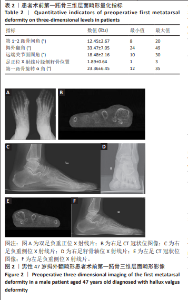

[21] KIMURA T, KUBOTA M, SUZUKI N, et al. Weightbearing Computed Tomography and 3-Dimensional Analysis of Mobility Changes of the First Ray After Proximal Oblique Osteotomy for Hallux Valgus. Foot Ankle Int. 2021;42(3):333-339.

[25] 王文成,张兴飞,许亚军. Scarf截骨横行截骨线倾斜角度与拇外翻矫形力度关系的3D骨骼重建分析[J]. 中国组织工程研究,2021, 25(27):4265-4270.